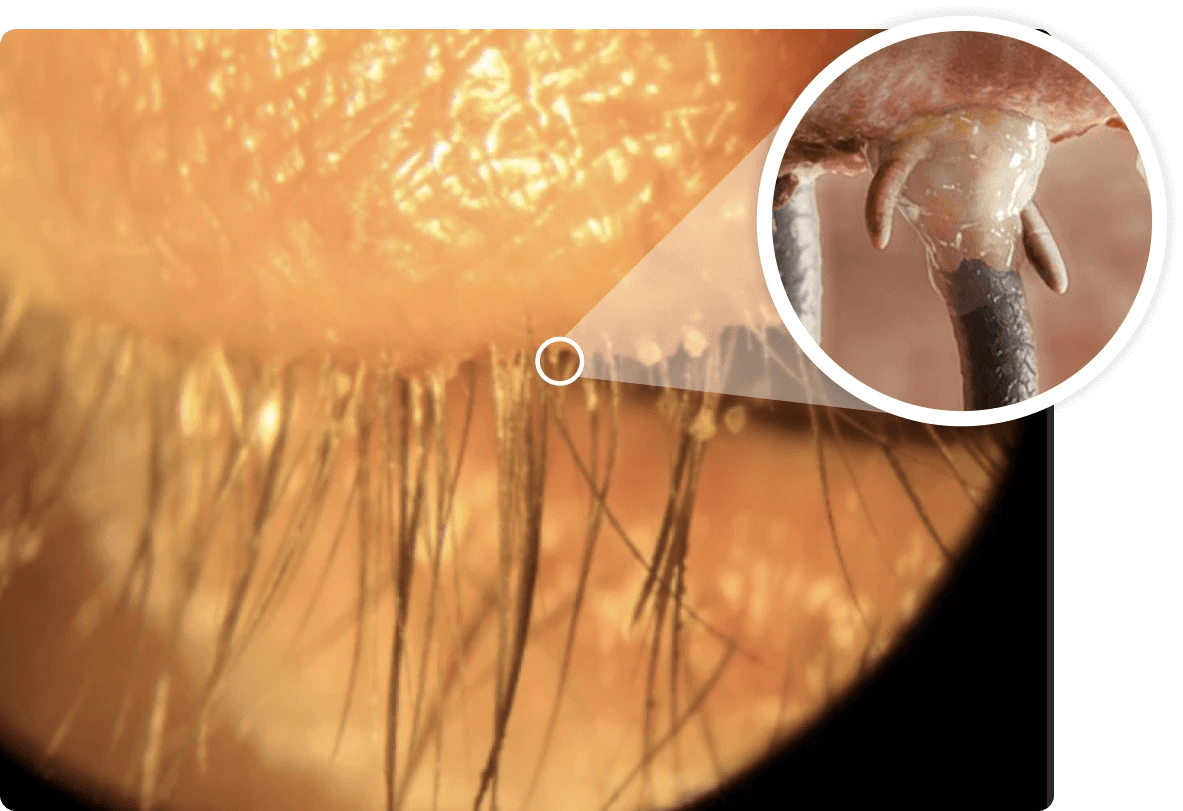

demodex blepharitis ungex demodex treatment

demodex blepharitis ungex demodex treatment 1024×681